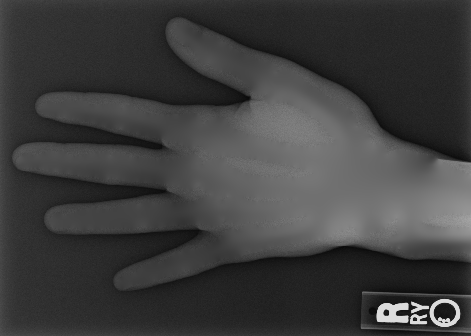

We performed three experiments for our method. First, we perform our method on several X-ray images, showing our method is not restricted by specific imaging objects. Second, we compared our method with image enhancement method and dehazing method, showing that our modification of the original dehazing indeed helps in this task. Third, we perform our method on a hand X-ray image dataset, showing its effectiveness and efficiency.

Several results from our method are shown in Fig. 7. The left column is the original input image. The right two columns are the soft tissue and bone image, respectively. It can be told that the soft tissue image is smooth as we assumed. Meanwhile, the bone image has better image contrast as desired. Moreover, our method can reach real-time performance on these X-ray images. The running time of our method on these images is reported in Table I.

In the third experiment, we applied our method on a hand X-ray image data set (RSNA), which contains more than 10,000 hand X-ray images. And the image has high resolution (usually larger than ). These images are collected from clinical applications. Therefore, we can apply our method on these practical images, showing the efficiency and effectiveness of our method on real high resolution images.

In each panel of Fig. 10, the input image (left) is decomposed into soft tissue (middle) and bone image (right) by our method. Although we only show the first ten images from the data set, the results for the rest images are similar.

The bone images have better image contrast since the parameter is theoretically guaranteed. Such enhancement can also be directly told by radiologists. Such enhancement is good for bone diagnosis in practical applications.